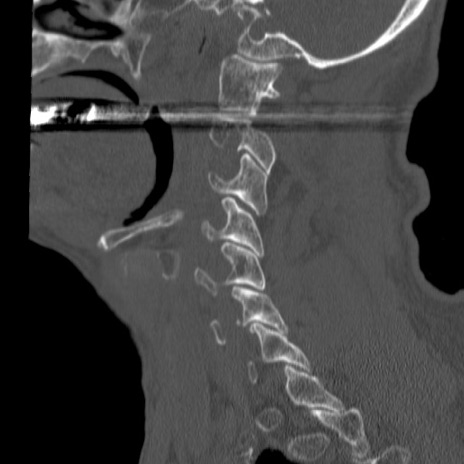

症例46 頚椎CT(矢状断像)

【症例】80歳代男性

【主訴】両側頚部〜上肢のしびれ

【現病歴】昨日、自宅内で転倒、その後より上記症状あり。意識障害なし。

【身体所見】両側上肢のallodynia(熱痛覚過敏)あり。MMTおよびDTRは正確な所見取れず。両上肢の挙上はなんとか可能。

異常所見と診断は?